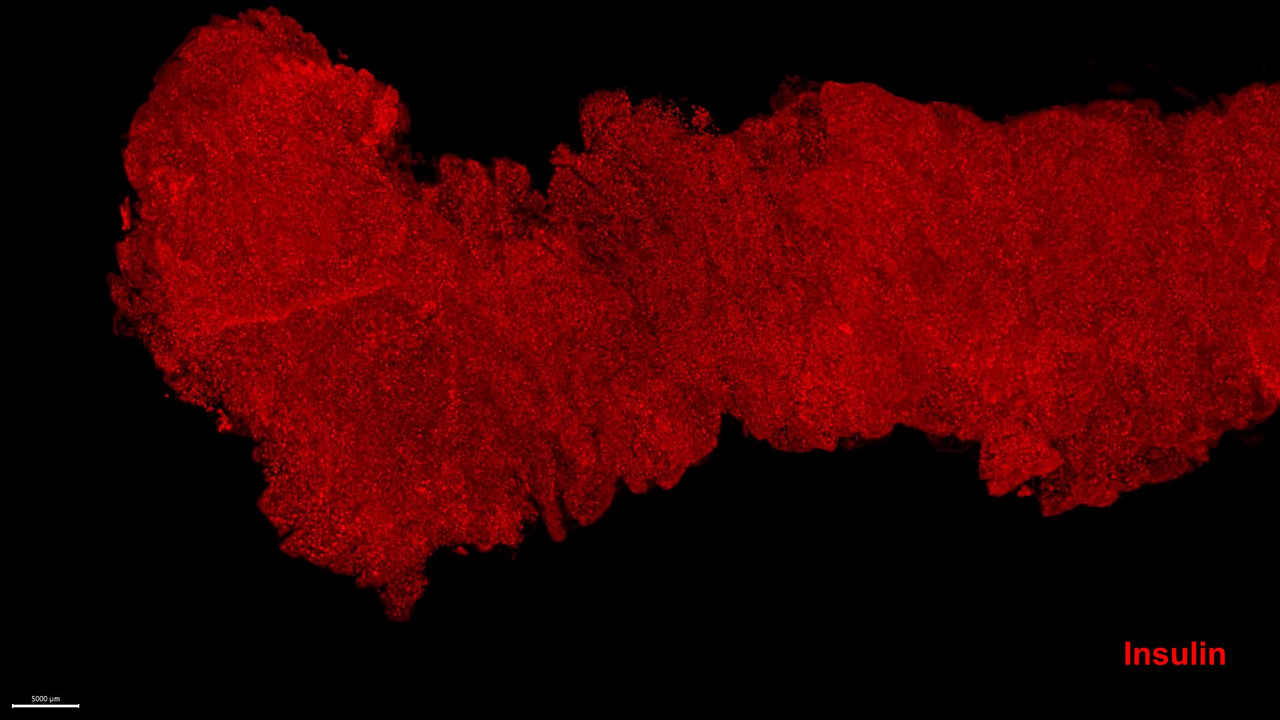

Filmen visar en mänsklig bukspottkörtel från en icke-diabetisk donator (〜15cm lång). Den innehåller 2.21 miljoner insulinproducerande Langerhanska öar (röda) med en total volym av 1,17 kubikcentimeter.

Ett nyckelorgan för utvecklingen av diabetes, en sjukdom som idag drabbar över en halv miljard människor, är bukspottkörteln. Den innehåller miljontals små cellgrupperingar, s.k. Langerhanska cellöar, som reglerar blodsockernivåerna i kroppen. Öarna innehåller framför allt celler som producerar hormonerna insulin och glukagon. Insulin insöndras i blodet och fungerar ungefär som en nyckel för att låsa upp kroppens celler så att de kan ta upp socker/energi i form av glukos efter en måltid. Glukagon i sin tur frigör glukoslager, då vi behöver tillskott av energi. Dessa båda celltyper kommunicerar även direkt med varandra för att den här regleringen ska fungera.

Forskarna visar nu, förutom nya data om hur de insulinproducerande cellerna är utspridda i bukspottkörteln, att till skillnad från vad man tidigare trott så saknas glukagonproducerande celler i så många som 50 % av de Langerhanska öarna med insulinceller.